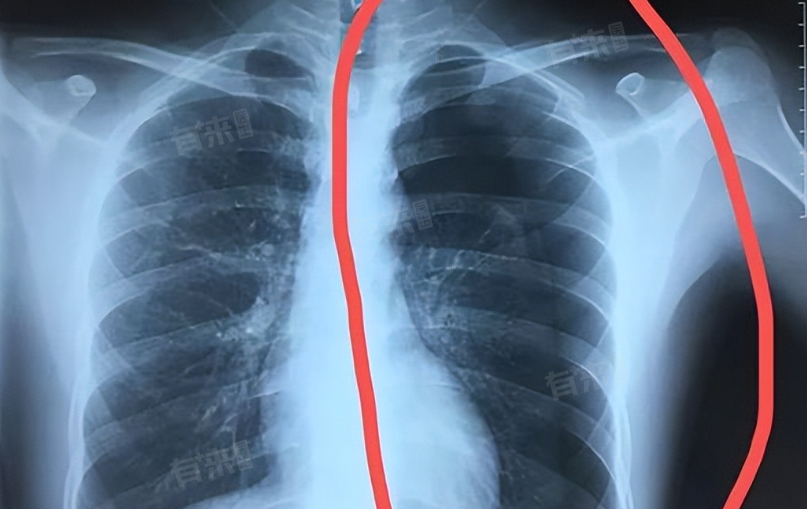

左侧气胸时,正确睡姿对缓解症状至关重要。半卧位可减轻胸闷,尤其适合已接受胸腔治疗者;向右侧卧则有助于气体交换,但需避免仰卧和左侧卧,以免加重症状。